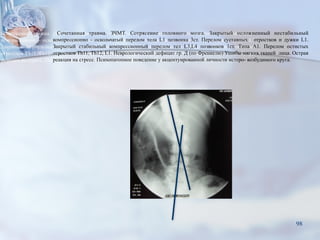

Сочетанная травма. ЗЧМТ. Сотрясение головного мозга. Закрытый осложненный нестабильный

компрессионно - оскольчатый перелом тела L1 позвонка 3ст. Перелом суставных отростков и дужки L1.

Закрытый стабильный компрессионный перелом тел L3,L4 позвонков 1ст. Типа А1. Перелом остистых

отростков Th11, Th12, L1. Неврологический дефицит гр. Д (по Френкелю) Ушибы мягких тканей лица. Острая

реакция на стресс. Психопатопное поведение у акцентуированной личности истеро- возбудимого круга.

Результаты КТ с 3D реконструкцией до операции

■1 – Ламинэктомия L1 позвонка.

Ревизия позвоночного канала.

■2 – Задний спондилодез системой

транспедикулярной фиксации

ChM(Polland) Th12, L2 позвонков с

боковой и задней редукцией тела

L1 позвонка.

КТ с 3D реконструкцией после операции

«DAMAGE CONTROL ORTHOPEDICS» ПРИ ПОЛИТРАВМЕ